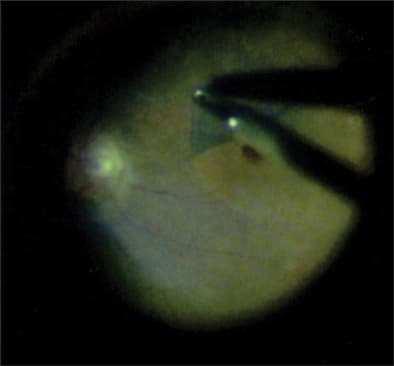

Another possible explanation for poor visual outcomes following anatomically successful macular hole surgery is ICG toxicity. Studies as well as practical experience have shown that the use of ICG to stain the vitreoretinal interface unequivocally facilitates the dissection of the outer layer of the posterior vitreous cortex and perhaps also some of the ILL of the retina (Figure 3). The reason that ICG is so effective probably results from the fact that not only does it stain the vitreoretinal interface, but it also alters its biophysical properties,19 enabling easier and more effective peeling. While closure rates are indeed increased with ICG, visual outcomes are at times disappointing, raising the specter of ICG toxicity.20,21 Studies22 have shown that ICG lingers in the fundus long after surgery. Possible mechanisms of toxicity include phototoxic as well as osmotic effects upon the neural retina22 (particularly retinal ganglion cells17), the optic disk,23 and the retinal pigment epithelium24 via apoptosis.25 There is, however, a postmortem study26 in pig eyes that found no retinal damage.

Figure 3. Membrane peel after ICG staining in macular hole surgery.

REPRINTED FROM MEYER CH, ED. VITAL DYES IN VITREORETINAL SURGERY – CHROMOVITRECTOMY. BASEL, SWITZERLAND; KARGER; 2008, WITH PERMISSION FROM KARGER.